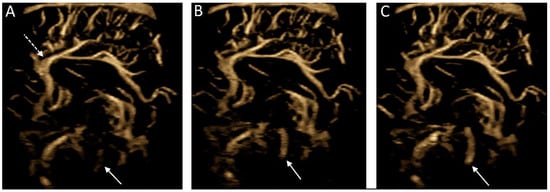

Another novel use of MVI is the detection of cerebrospinal fluid flow, the velocity of which is often below the threshold of typical Doppler imaging (Figure 7). One case study has successfully used MVI to demonstrate cerebrospinal fluid flow in post-hemorrhagic hydrocephalus [47]. Further work is needed to understand the nature of flow (i.e., velocity, turbulence, composition) detectable using MVI such that nonvascular applications of MVI be applied for diagnostic and/or prognostic utility.

Figure 7.

Microvascular imaging of the brain acquired in a in a midsagittal plane. (A–C) Consecutive images were acquired demonstrating cerebrospinal fluid flow within the cerebral aqueduct (solid arrows). Note is made of the anterior cerebral artery and its branches (dashed arrow).